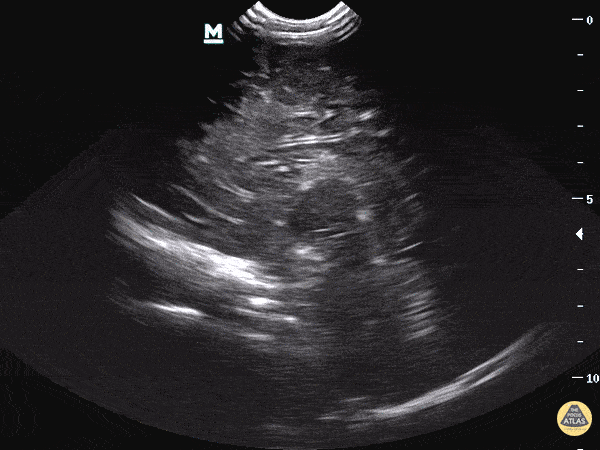

Pediatrics - Head Imaging - Sagittal View

The sagittal plane has the indicator marker facing the anterior aspect of the face and the ultrasound beam is swept in either the left to right or right to left direction of the patient’s shoulders. Please see our blog post for further information on this topic. Dr. Sathya Subramaniam - Childrens Hospital of Philadelphia Pediatric, EM Ultrasound